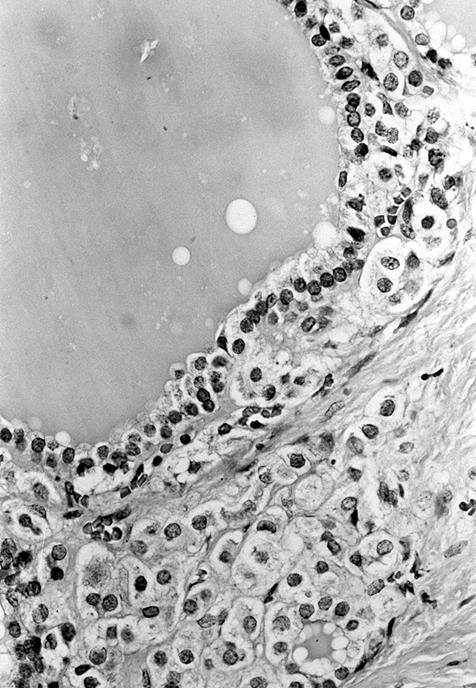

Microscopic (histologic) description

- Wide variety of morphology, can mimic any other thyroid malignancy

- Round, plasmacytoid, polygonal or spindle cells in nests, cords or follicles; often mixtures of these cells

- Round nuclei with finely stippled to coarsely clumped chromatin and indistinct nucleoli, occasional nuclear pseudoinclusion

- Eosinophilic to amphophilic granular cytoplasm due to secretory granules

- Stroma has amyloid deposits from calcitonin, prominent vascularity with glomeruloid configuration or long cords of vessels (Am J Surg Pathol 1995;19:642), coarse calcifications, occasional psammoma-like bodies

- C cell hyperplasia present in familial but not sporadic cases

- Follicular variant: has follicles containing eosinophilic secretion (Histopathology 1983;7:83)

Microscopic (histologic) images

Contributed by Shuanzeng Wei, M.D., Ph.D., Joseph Christopher Castillo, M.D. and Mark R. Wick, M.D.

AFIP images

Images hosted on other servers: